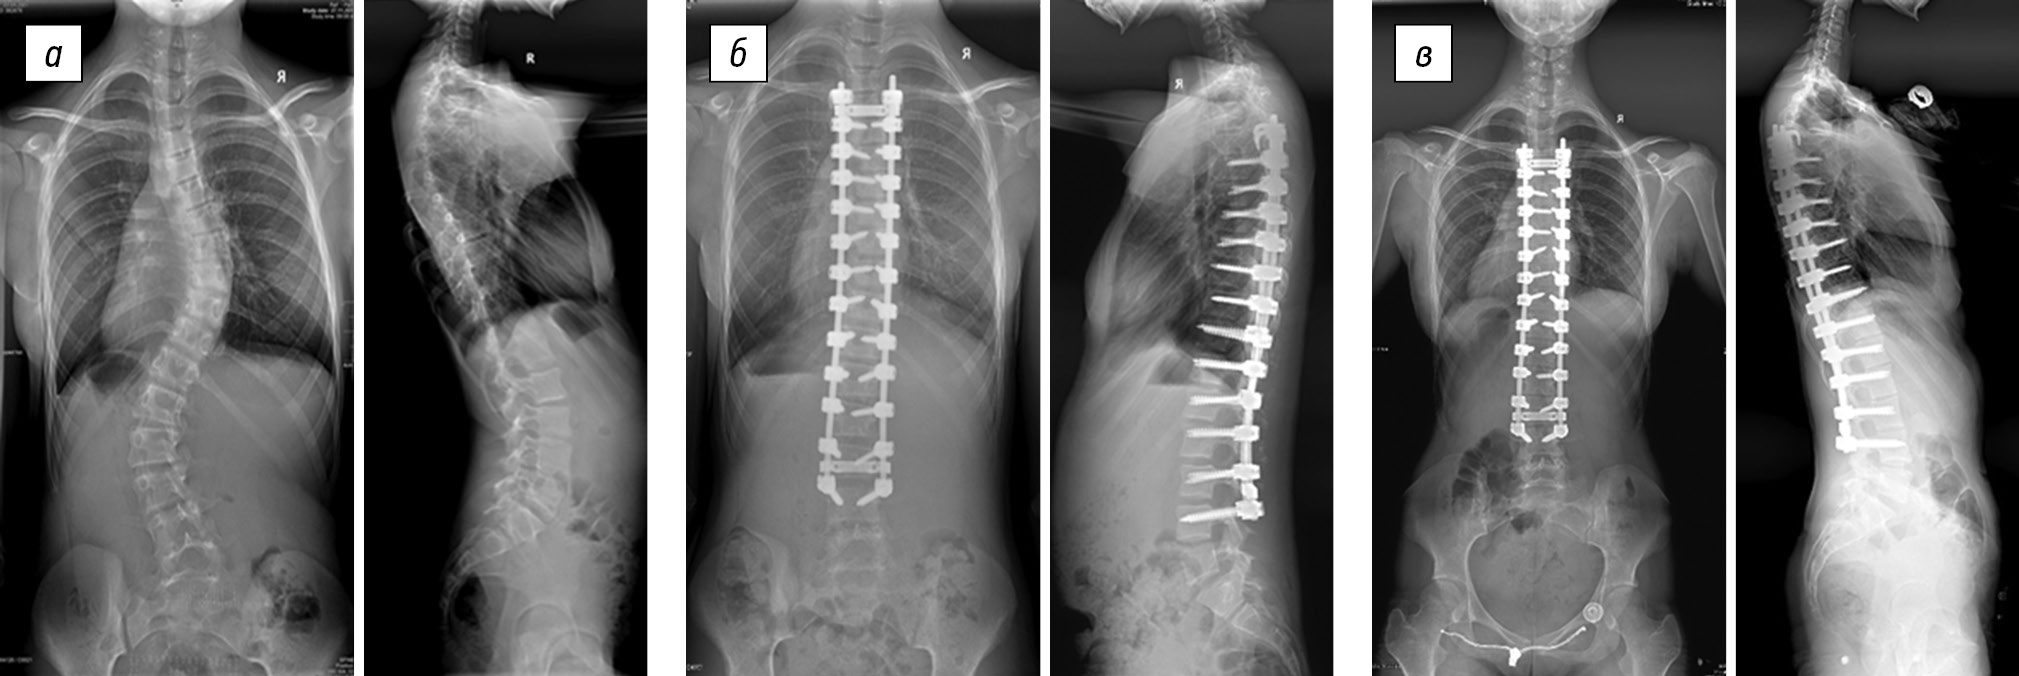

In group 1 (Table 1), the preoperative size of the thoracic scoliotic curve was 61.0 ± 13.6°, and the postoperative thoracic scoliotic curve was reduced to 18.5 ± 10.4° (p < 0.05). The value of the primary correction was 42.5 ± 9.1°, which was found in 70.8 ± 12.2% of the cases (p < 0.05). Postoperative progression was on average 5.9 ± 3.2°, which was found in 14.3 ± 8.3% of the cases (Fig. 1). The average patient age was 12.6 ± 0.7 years, and the average duration of postoperative follow-up was 46.5 ± 25.6 months.

Fig. 1. Radiographs of a 13-year-old patient in two views: a — preoperative image of the right-sided thoracic scoliotic deformity of IV degree (74° according to Cobb) with lumbar anti-curvature (47°), with thoracic kyphosis of 24° and lumbar lordosis of 67°; b — surgical correction of scoliotic deformity of the spine using hybrid fixation without ventral intervention results in main thoracic curve of 30°; lumbar anti-curvature of 10°, thoracic kyphosis of 18°, and lumbar lordosis of 60°; c — X-ray control 3 years after the surgery revealed main thoracic curve of 46°, lumbar anti-curvature of 10°, thoracic kyphosis of 18°, and lumbar lordosis of 76°